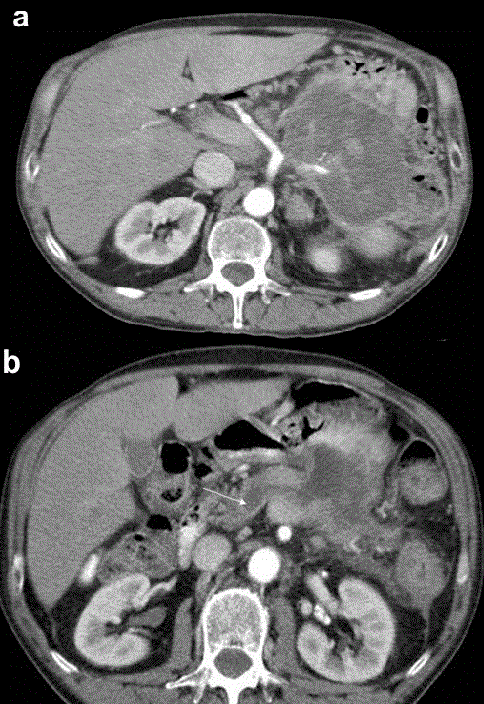

| Figure 1.Preoperative contrast-enhanced CT-scan at the celiac axis level. a. A large low-density mass in the pancreatic body and tail infiltrating the posterior gastric wall, the splenic flexure of the colon and the spleen. The amputation of the splenic artery is evident. b. Dilated main pancreatic duct (white arrow). |